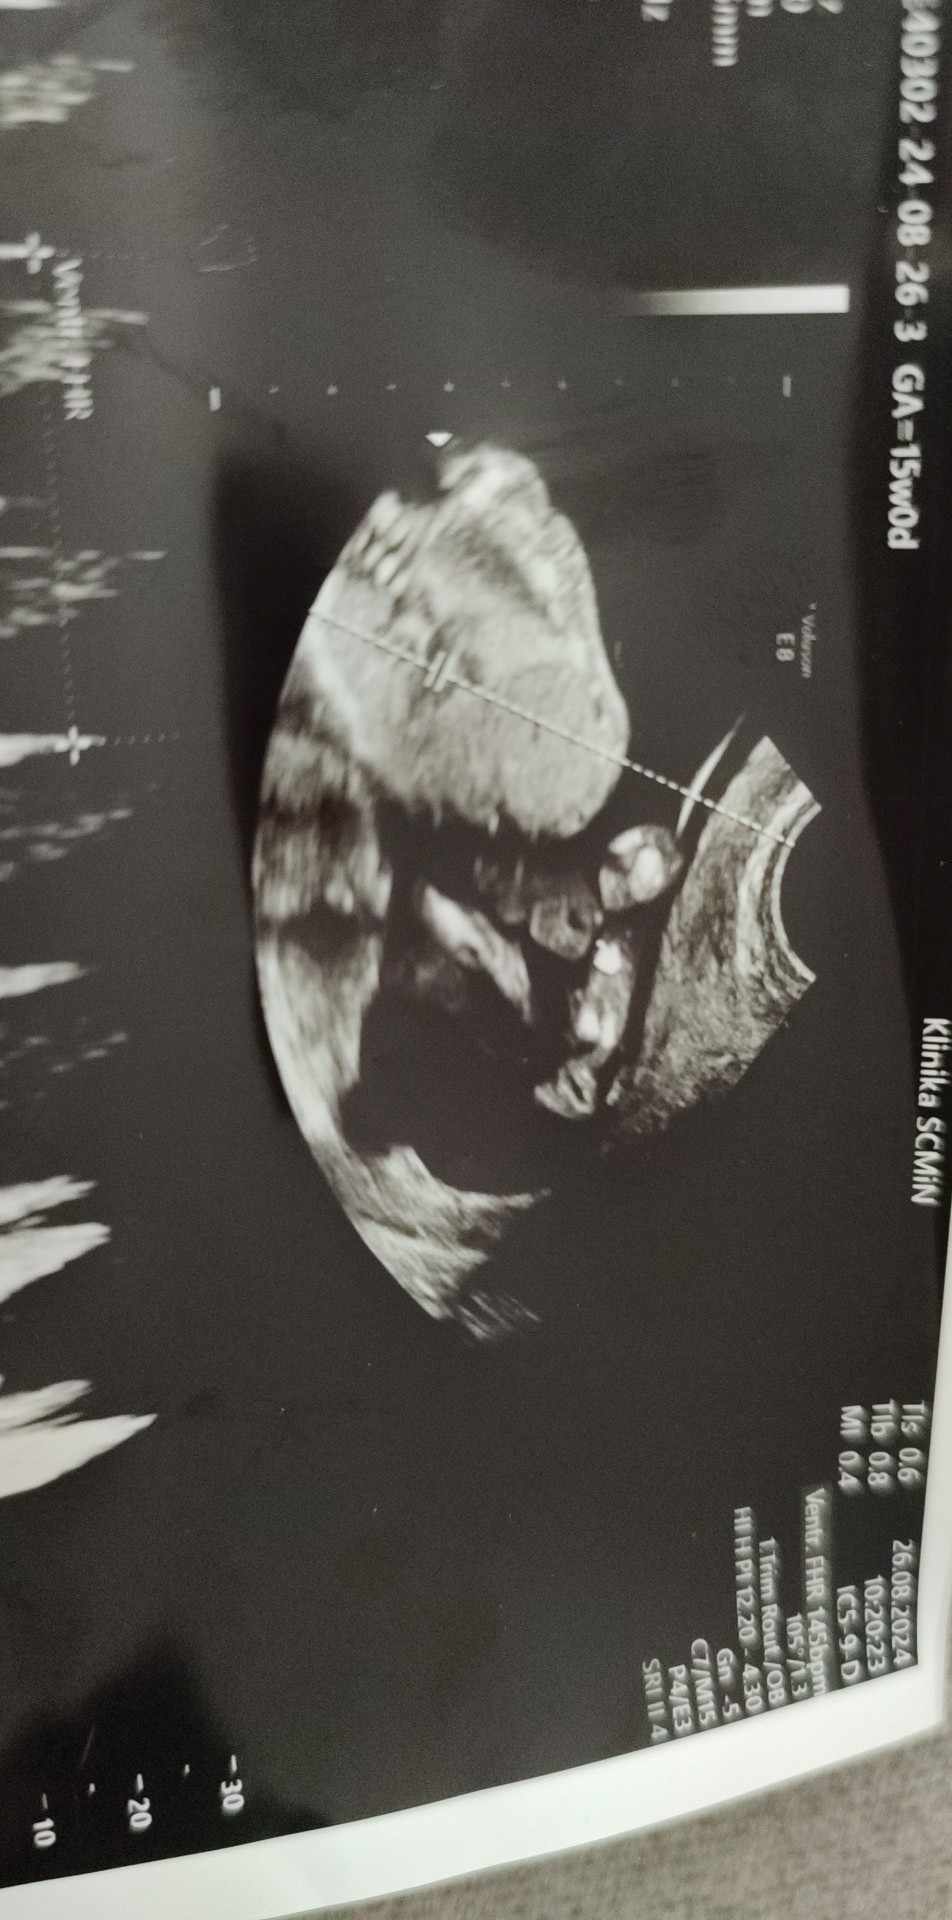

Hej dziewczyny czy tu widać że będzie dziewczynka bo Pani ginekolog powiedziała że na 100% dziewczynka a ja jakoś mam przeczucie że się myli

• IMG_20240826_122422.jpg

128,7 KB · Wyświetleń: 91